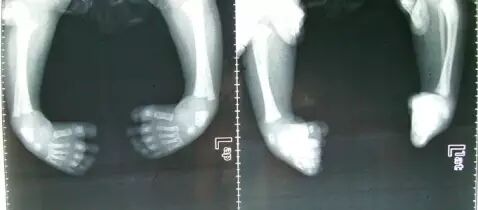

到医院拍片检查显示:菲菲左侧踝骨发育不良,双足内翻,被诊断为“马蹄内翻畸形”!

7个月的宝宝坐学步车,脚不能完全着地,只能用脚尖触地滑行,时间一长就形成前脚掌触地的踮脚走路姿势,逐渐形成“马蹄内翻畸形”。而且学步车过轻,婴幼儿在快速移动过程中,产生摔伤、扭伤的情况,也屡见不鲜。

畸变原理:小孩的骨骼和成年人不一样,他们需要在学习[躺→坐→爬→走]的过程中,逐步获得与行走相匹配的适应能力。行走是负重运动,当关节肌肉发育还未达到负重的要求时,过早起步就会影响孩子下肢的发育,导致“X”或“O”的畸形腿。